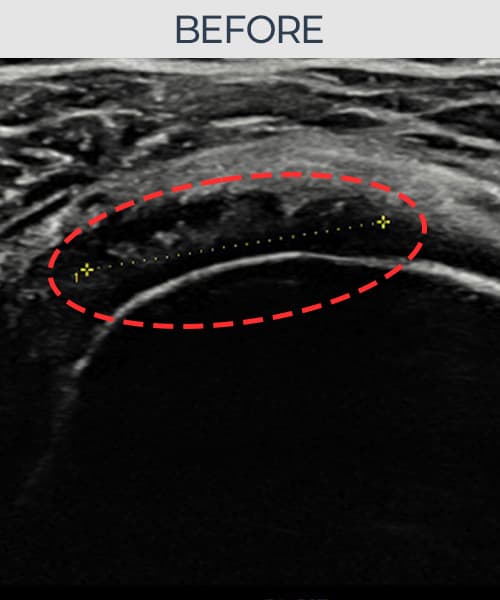

[経過期間: 23.07.18~23.09.14]

[縫縮術] 超音波検査にて左 棘上筋腱 광범위 部分断裂(15mm × 6mm (腱厚の約70%欠損))を確認。縫縮術施行後、腱の連続性が回復し、日常生活に復帰されました。